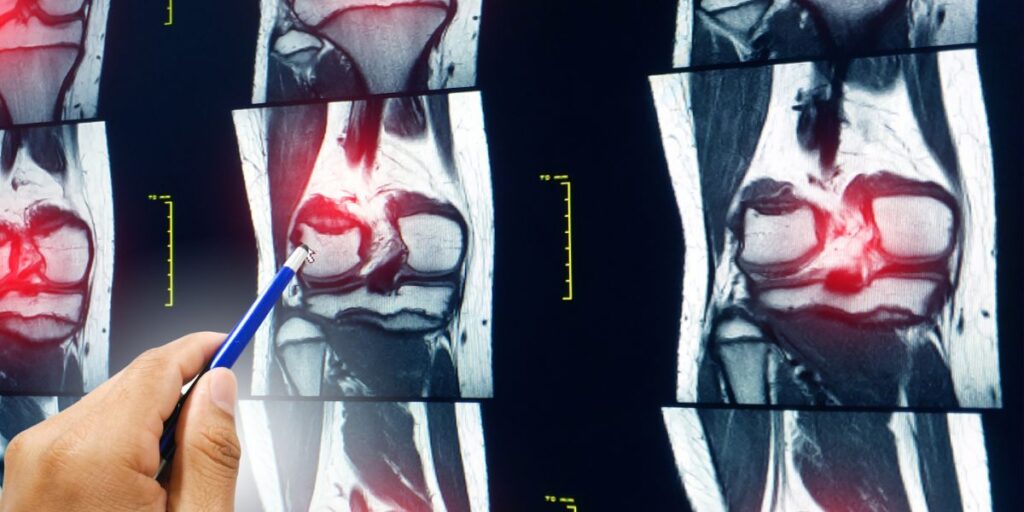

La Risonanza Magnetica Ginocchio svolge un ruolo cruciale nella valutazione di diverse patologie. Grazie alla qualità delle immagini, i medici possono rilevare lesioni, infiammazioni e degenerazioni, facilitando una diagnosi accurata e la pianificazione di trattamenti mirati.

La Risonanza Magnetica Ginocchio permette ai medici di osservare con precisione le strutture anatomiche del ginocchio. Le immagini dettagliate rivelano lo stato dei legamenti, dei tendini, dei muscoli e delle cartilagini, facilitando una valutazione complessiva dell’articolazione.

La Risonanza Magnetica Ginocchio è utile per identificare diverse patologie, tra cui lesioni ai legamenti, distorsioni o strappi dei menischi, infiammazione delle cartilagini e problemi vascolari. Questa procedura diagnostica è fondamentale per una gestione efficace della salute del ginocchio.